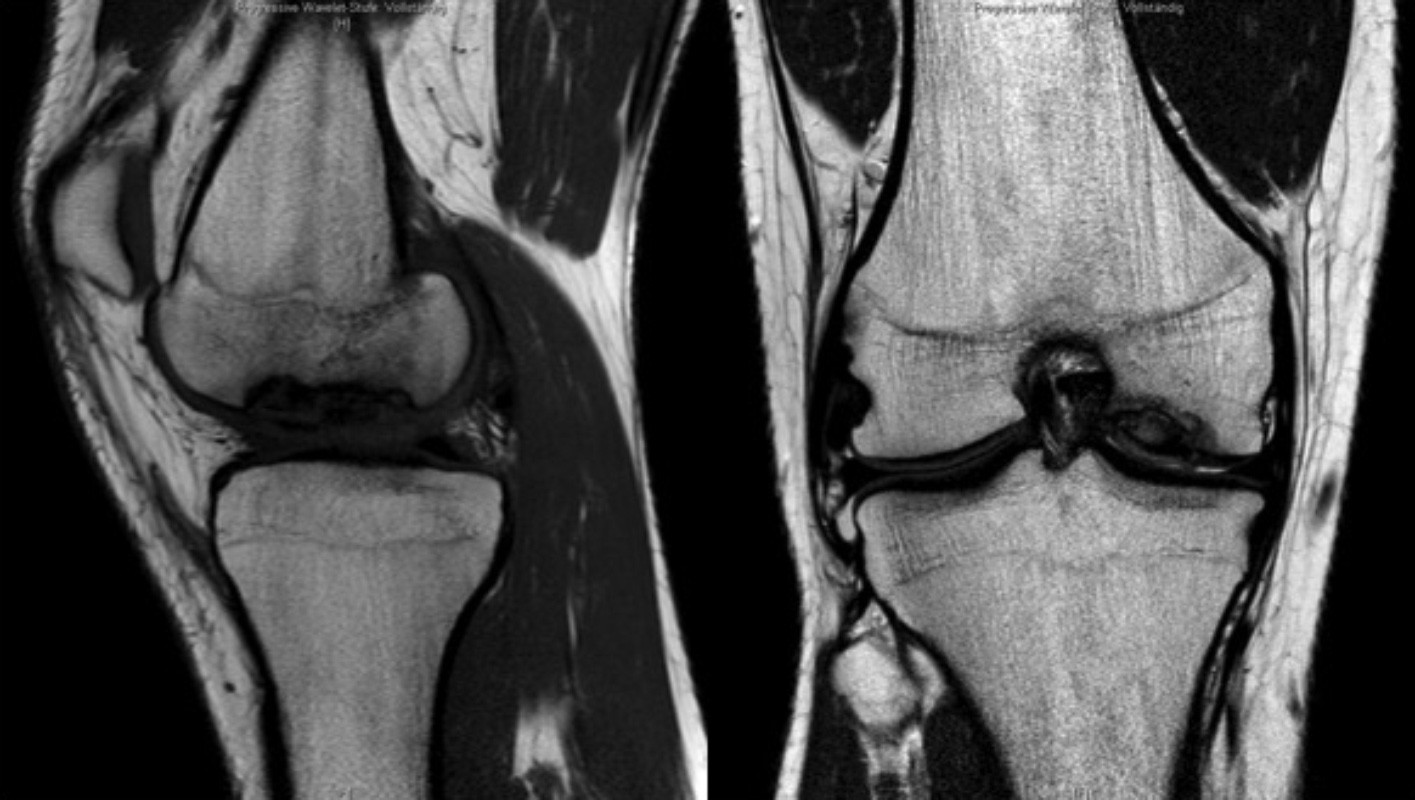

Kniegelenk mit sogenannter "Osteochondrosis dissecans"

Durch eine Durchblutungsstörung des zugrundeliegenden Knochens kommt es zum Absterben des Gelenkknorpels in einem scharf begrenzten Bereich.